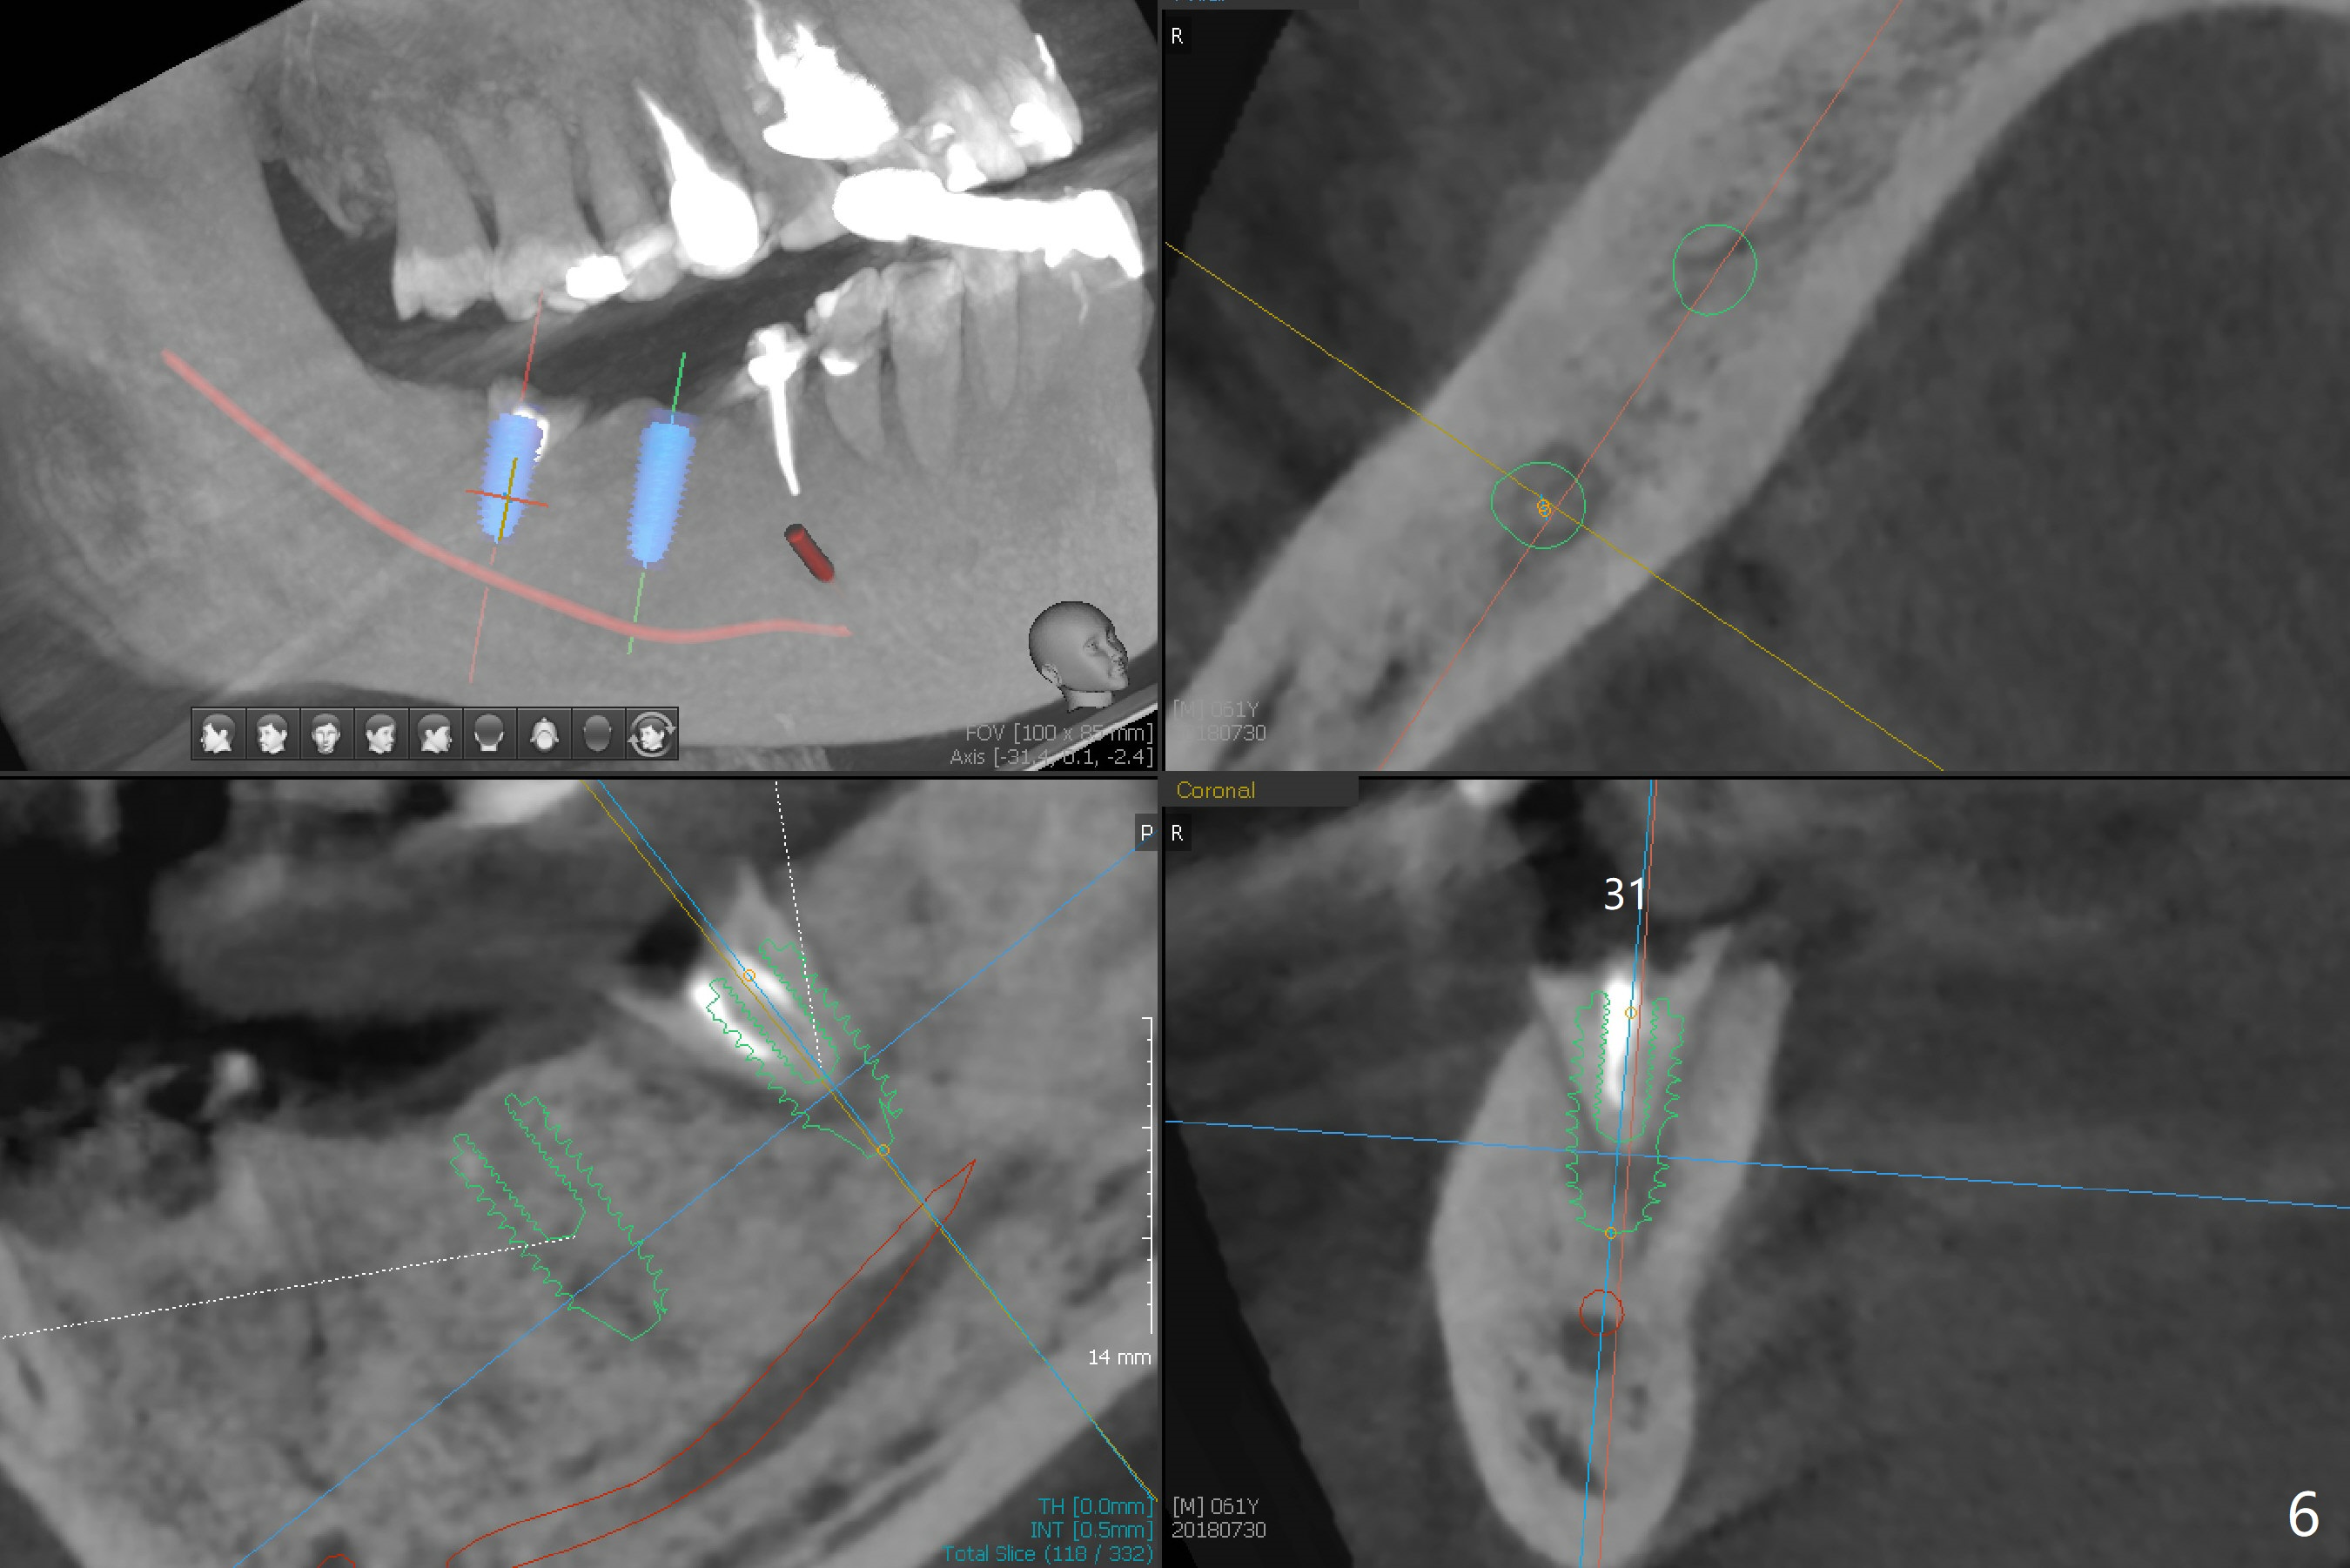

My question is have you measured the how much remaining bones are left at the extraction socket. How much bone depth is left after the root extraction? Do you think the implant could get enough fixation after the extraction? Jennifer It is a good question. As today's CT indicates (07/30/2018), there is ~ 3 mm bone for primary stability with ~ 1 mm clearance (Fig.3-6). Because of the tapered implant, ~5 mm of the implant will be able to contact the native bone if the implant is lingually placed (Fig.6). If you feel it too much a risk, still make a guide for #31 so that an anchor pin can be placed at #31 residual roots for fixation (a new idea?). Make sure that the distal portion of the guide contacts the #31 residual root stump for stability, which is superior to a guide resting on the soft tissue. I have had experience placing implants free hand in this situation. The guide will be great help. I will use judgment in surgery. The worst scenario is socket preservation. Thanks for consideration and design.